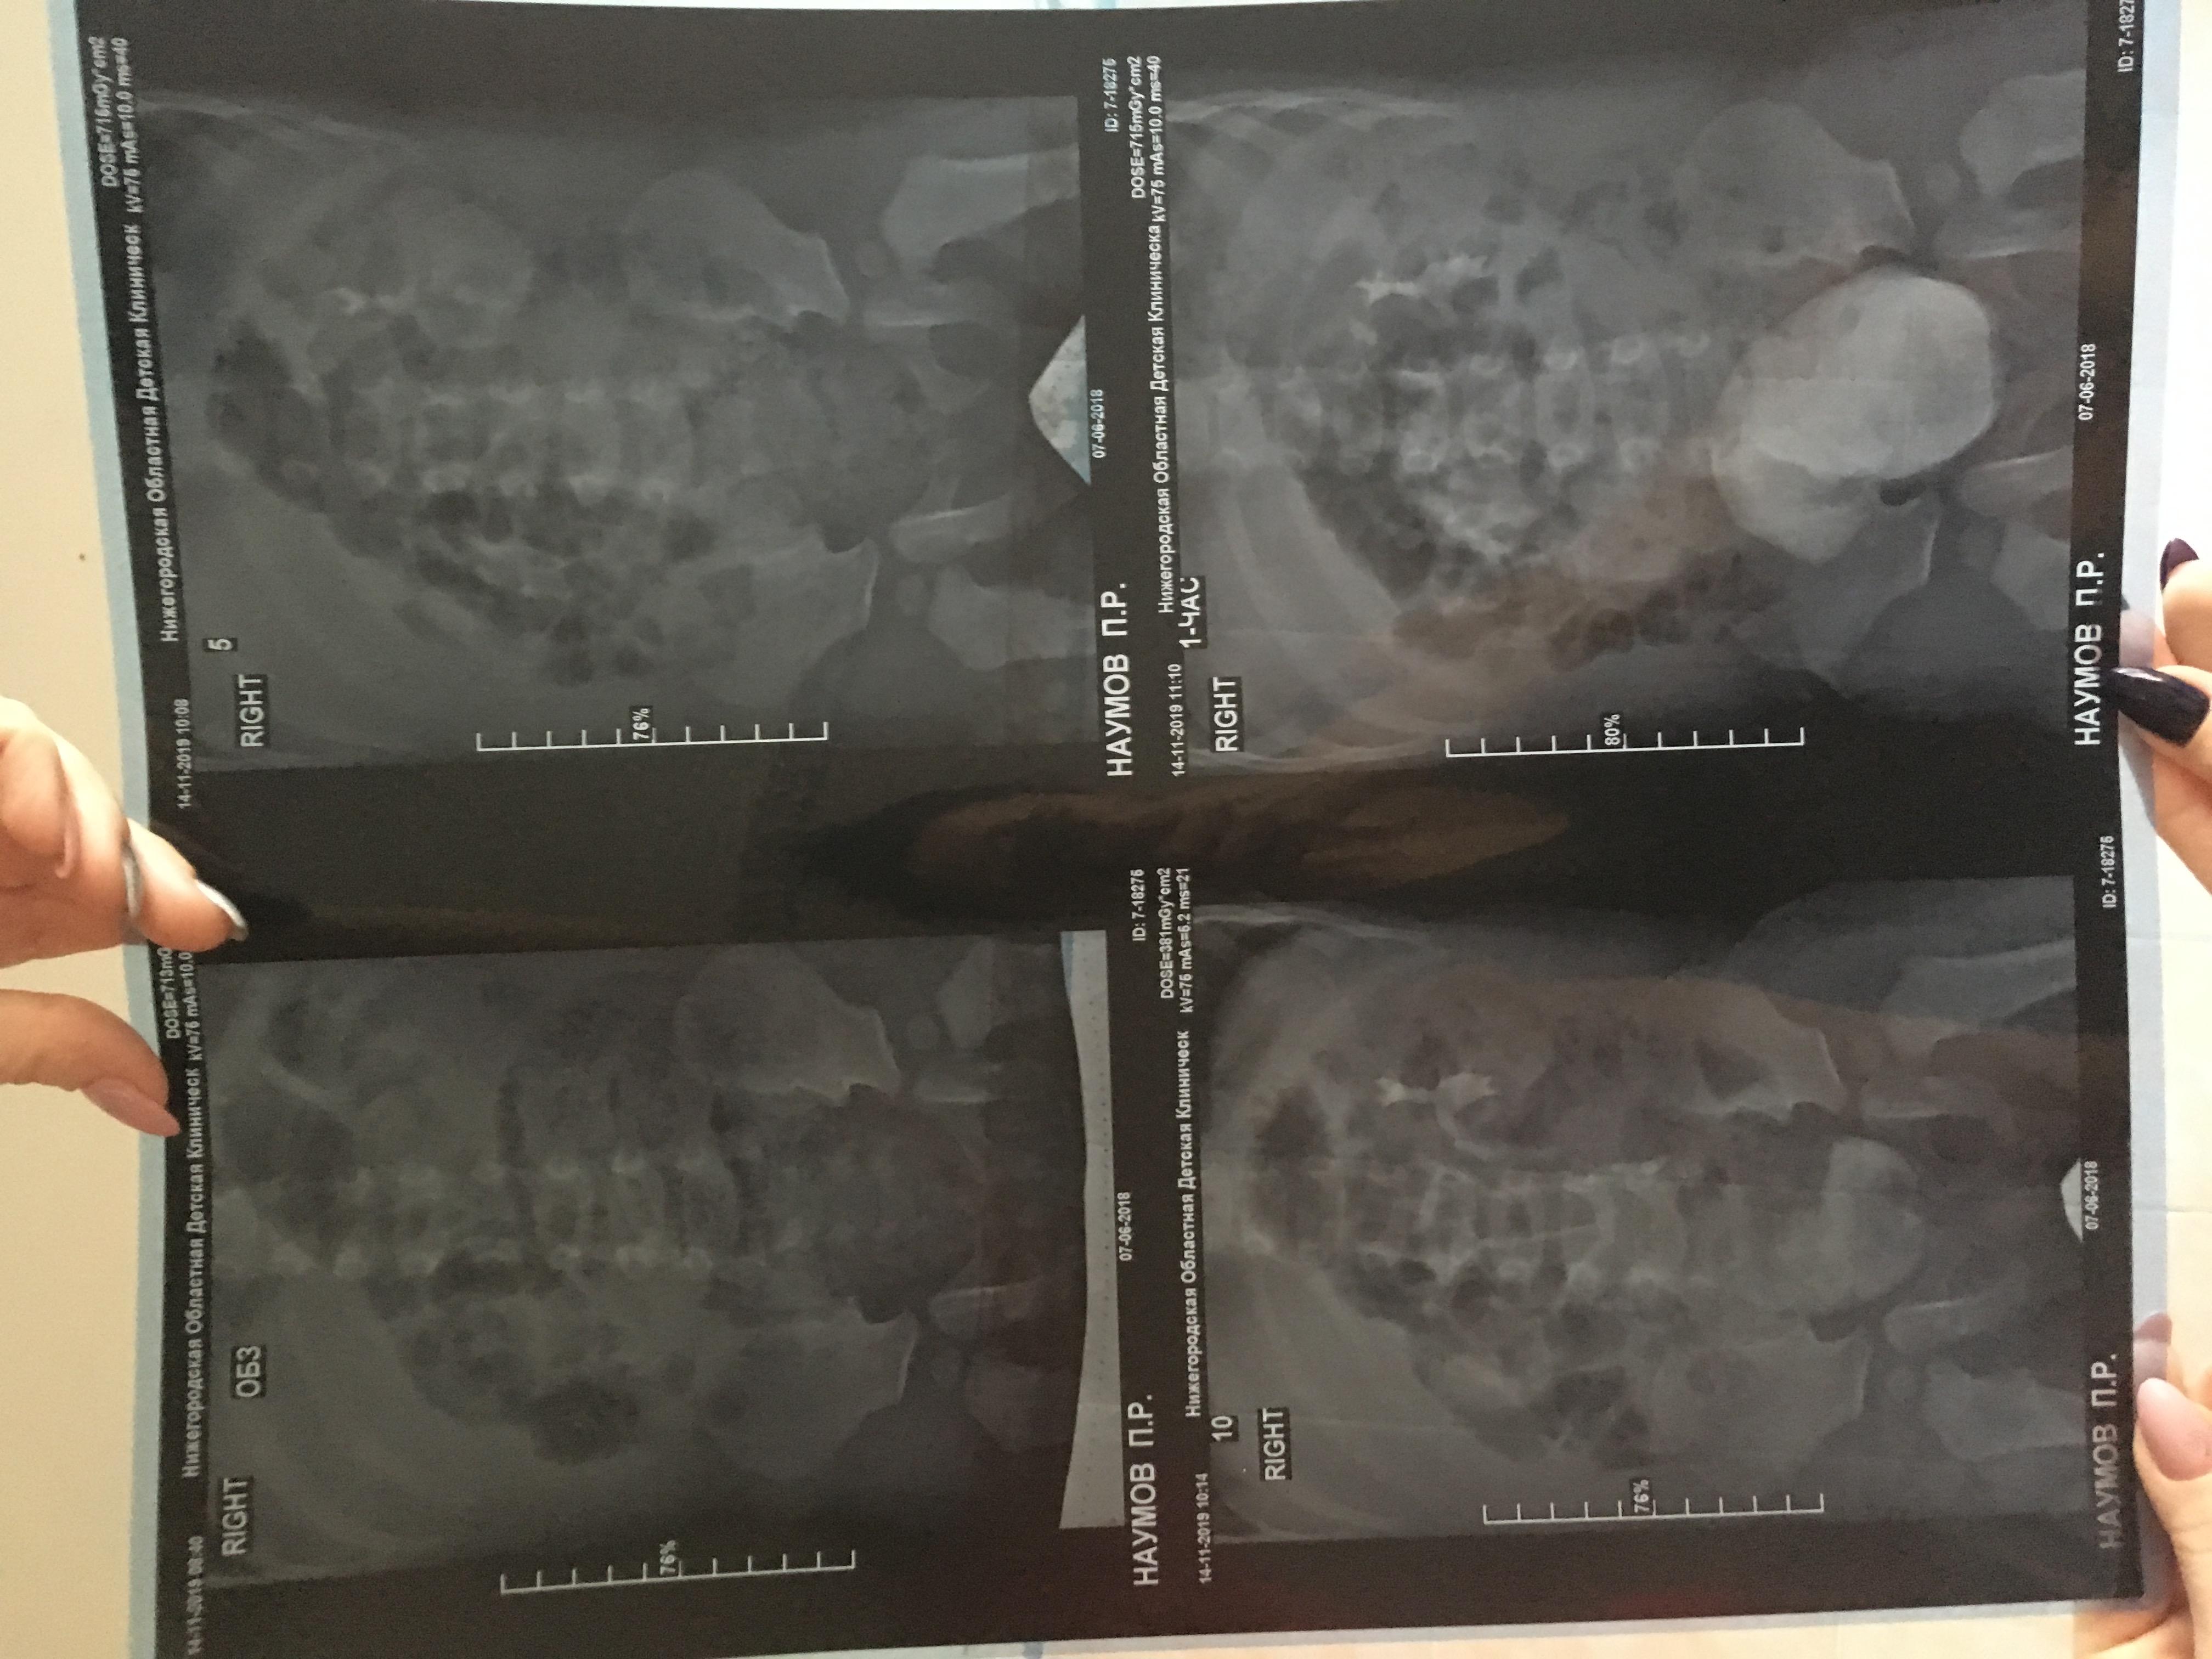

Здравствуйте , с Рождения поставлен диагноз уретерогидронефроз , пмр4 ст. Пол года назад сделали операцию по Коэну, но улучшений нет , рефлюкс стал 3 ст, а функция почки снижена . Лечащий хирург сказал, что ничего предпринимать не нужно, только наблюдение и высокая вероятность сморщивание почки и в последствии ее удаление. Скажите пожалуйста действительно ли уже не спасти почку ?!

Прилагаю снимки до операции и после операции.